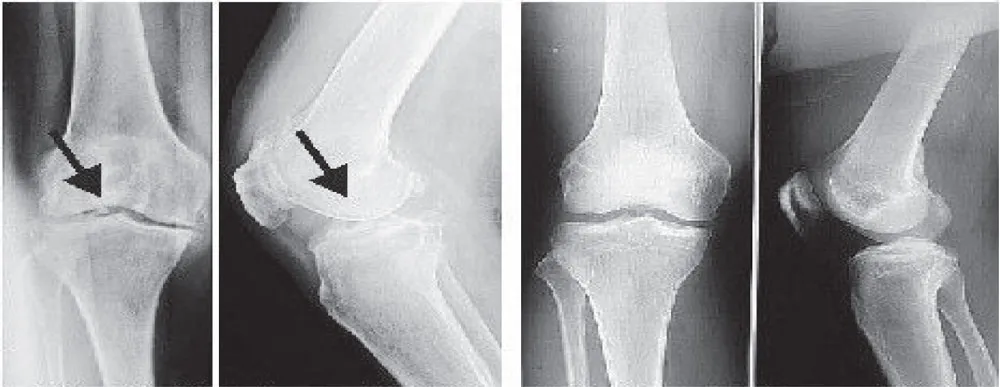

Trước và sau khi sử dụng